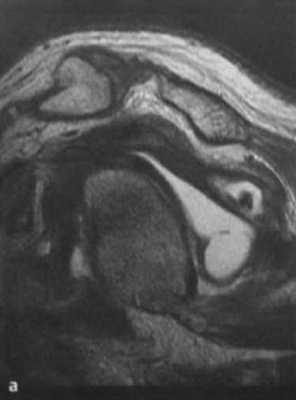

а-с Запущенная деструкция вращательной манжеты с предшествующими дегенеративными изменениями. Разрыв сухожилий надостной и подостной мышц, медиальное смещение длинного сухожилия двуглавой мышцы, выраженная атрофия всех мышц, составляющих вращательную манжету. (а) Сагиттальная МРТ. Генерализованная атрофия, каудальное смещение брюшка подлопаточной мышцы и смещение сухожилия двуглавой мышцы в полость сустава.